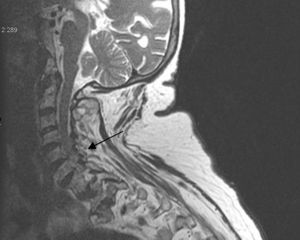

La afectación del esqueleto axial por condrocalcinosis ha estado asociada a depósitos cálcicos en disco intervertebral, ligamento amarillo, articulaciones facetarias e incluso articulaciones sacroilíacas. La calcificación del ligamento transverso del atlas (figs. 1-3) es una manifestación menos frecuente y se ha denominado síndrome de Crown Dens; constituye un cuadro clínico asintomático en la mayoría de las ocasiones, pero también puede estar asociado con brotes agudos de dolor cervical, rigidez y fiebre con las connotaciones de dificultad diagnóstica añadidas en estos casos.

Presentamos el caso de una mujer de 82 años que consulta por dolor cervical intenso, mal controlado con analgésicos. Como antecedentes de interés destaca la presencia de una fibrilación articular anticoagulada, espondiloartrosis y condrocalcinosis radiológica en rodillas. En la exploración realizada destaca un dolor espontáneo en la región cervical, irradiado a la región occipital y mastoidea, con rigidez y bloqueo doloroso a la movilización del cuello y sin alteraciones neurológicas.

En los estudios radiológicos realizados destaca la aparición de una espondiloartrosis cervical y calcificaciones en el ligamento transverso del atlas y ligamentos alares a nivel de la articulación atlo-axoidea (fig. 4).